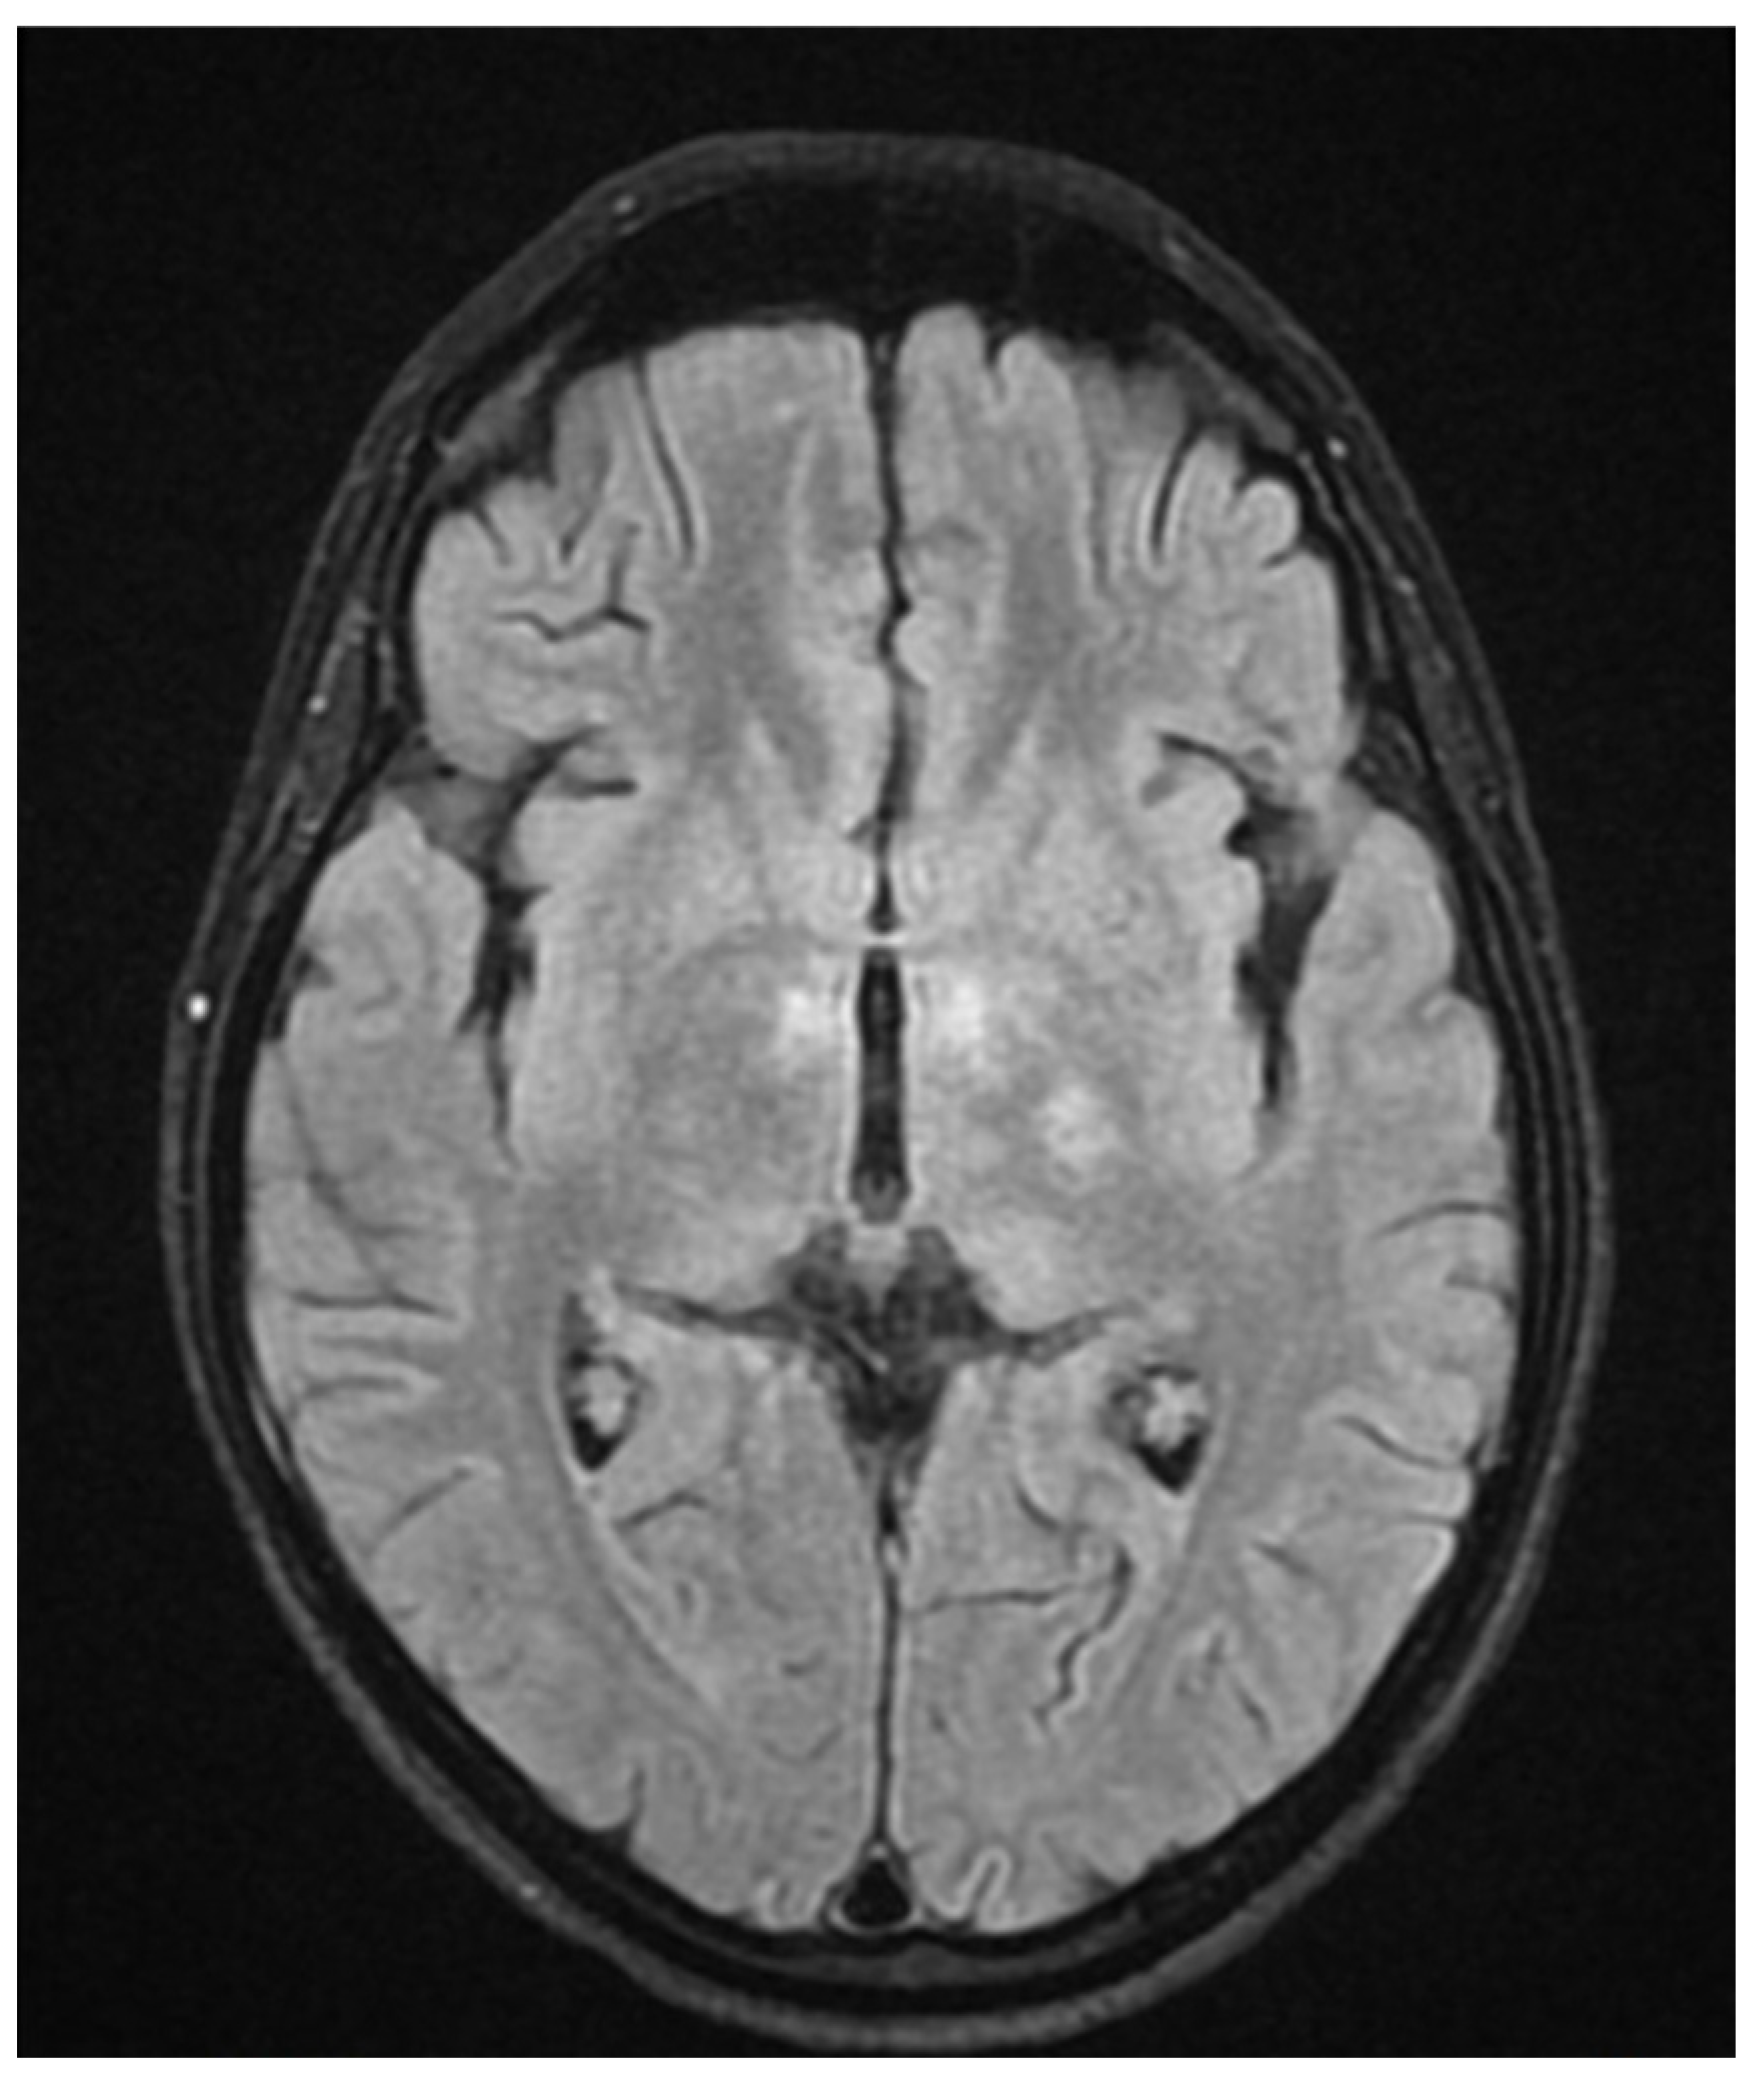

During hospitalization in the neurology ward, Holter EEG was performed in which seizure episodes corresponded to changes in the recording. Interictal EEG showed rapid activity followed by slow theta waves and several sharp and slow wave complexes (Figure 1 and Figure 2). Topiramate was added to valproic acid at a target dose of 2 mg/kg of body weight. Gradual seizure relief was observed in the following weeks, and there were no other neurological manifestations for another nine months. After that time, in December 2021, the patient was admitted to the pediatric ward due to impaired consciousness and persistent vomiting, followed by paresis of the lower limbs. A brain MRI was performed, which showed “T2/FLAIR images reveal poorly defined areas of increased signal in the brain’s white matter, both above and below the tentorium, as well as in the periventricular and subcortical regions. These areas correspond to low signal regions in T1 images. The largest change area measures 19 × 14 mm and is located in the right middle cerebellar peduncle, which merges with changes observed in the pons. Additionally, there is a lesion in the right thalamus, measuring 10 × 24 mm, along with numerous scattered foci in the corona radiata and between the basal nuclei. Overall, the imaging findings primarily suggest acute disseminated encephalomyelitis (ADEM)” (Figure 3 and Figure 4). Cerebrospinal fluid examination revealed oligoclonal bands and an elevated protein level of 118.5 mg/dL (reference range: 15.0–45.0 mg/dL) and a slightly elevated leukocyte level of 29/mm3 (lymphocytes 72.4%, neutrophils 27.6%).

Figure 2.

EEG recording: postictal theta waves (December 2020).